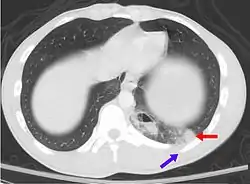

| A CT scan showing a pulmonary contusion (red arrow) accompanied by a rib fracture (purple arrow) | |

Computed tomography

Computed tomography (CT scanning) is a more sensitive test for pulmonary contusion,[6][33] and it can identify abdominal, chest, or other injuries that accompany the contusion.[38] In one study, chest X-ray detected pulmonary contusions in 16.3% of people with serious blunt trauma, while CT detected them in 31.2% of the same people.[45] Unlike X-ray, CT scanning can detect the contusion almost immediately after the injury.[43] However, in both X-ray and CT a contusion may become more visible over the first 24–48 hours after trauma as bleeding and edema into lung tissues progress.[46] CT scanning also helps determine the size of a contusion, which is useful in determining whether a patient needs mechanical ventilation; a larger volume of contused lung on CT scan is associated with an increased likelihood that ventilation will be needed.[43] CT scans also help differentiate between contusion and pulmonary hematoma, which may be difficult to tell apart otherwise.[47] However, pulmonary contusions that are visible on CT but not chest X-ray are usually not severe enough to affect outcome or treatment.[37]